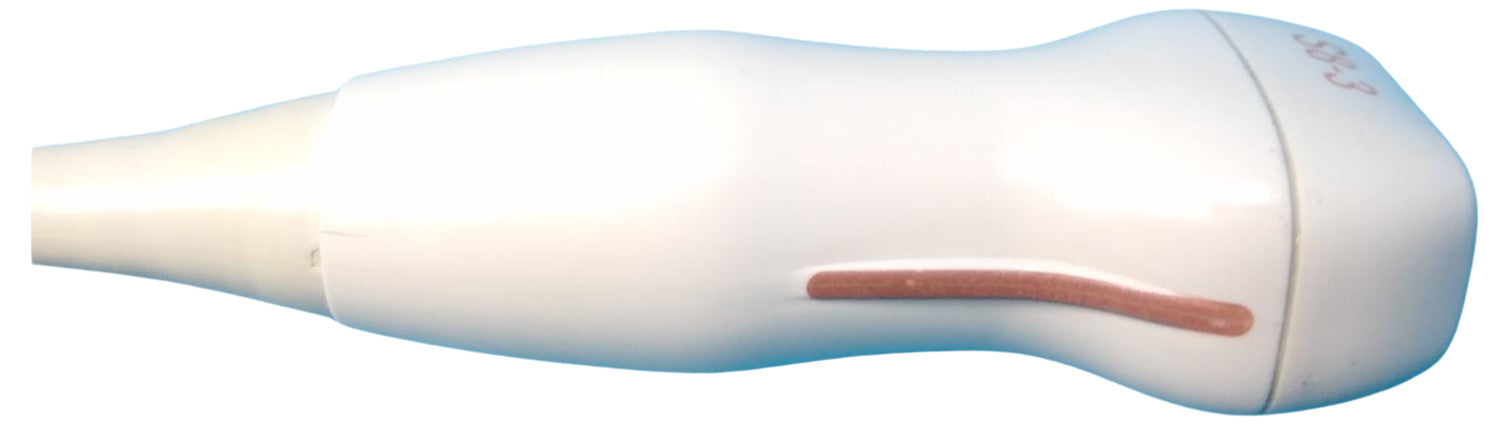

Probe is in good condition no compatible ultrasound to test the item. For the power cord, if you see a separate picture of the power cord, you'll receive it. Otherwise, we used the power cord only to test the item.